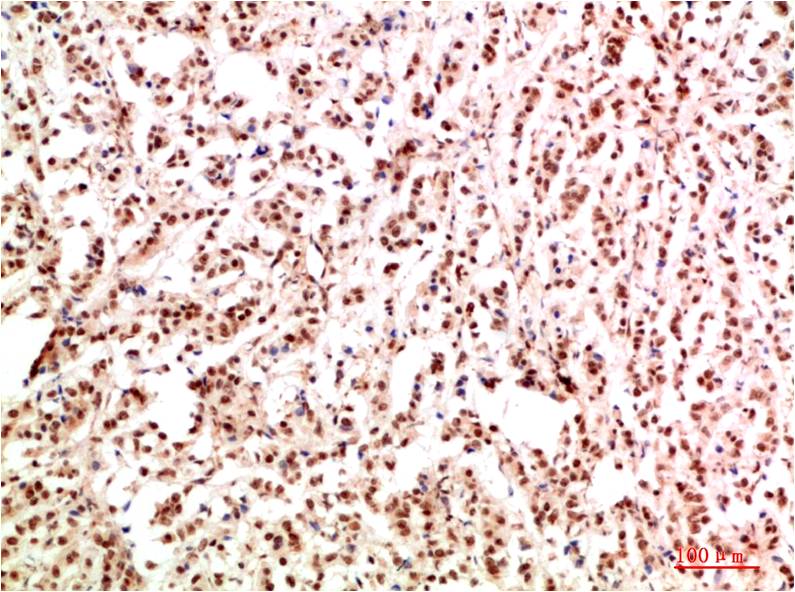

c-Jun Mouse Monoclonal Antibody(4G10)

Applications :IHC

| Recommended dilutions: | IHC 1:100-200 |

| Specificity: | The c-Jun Mouse Monoclonal Antibody can detects endogenous c-Jun proteins. |